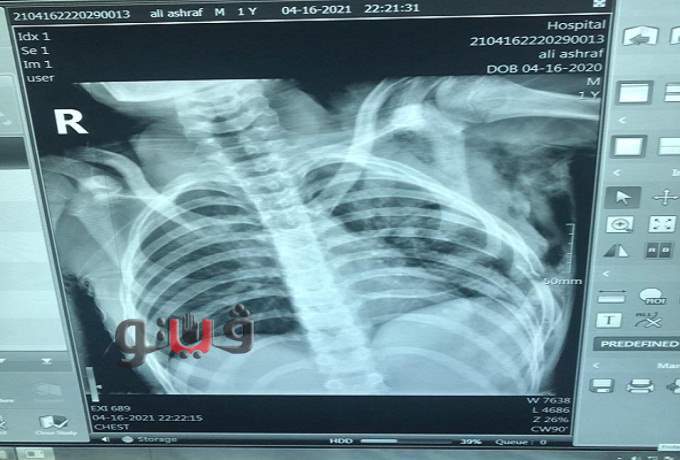

استقبلت مساء أمس حالة لطفل يبلغ من العمر 14 عاما ومقيم بمركز اهناسيا يعاني من

فقدان بالوعي وانخفاض في نسبة الأكسجين بالدم إثر حادث سير.

جروح عميقة بالصدر

وبالكشف الطبي وعمل الفحوصات اللازمة تبين وجود جروح عميقة بالصدر وعضلات الصدر وتكسير بالضلوع وخروج للرئة مع نزيف واسترواح هوائي وعلى الفور تم نقله إلي غرفة العمليات.